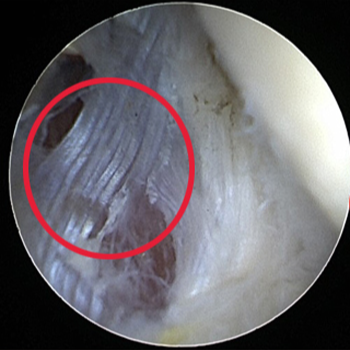

변성된 힘줄(건)을 제거하고 재생을 유도하는 수술

관절내시경 수술 전

관절내시경 수술 후

ㆍ환자 동의를 받은 자료이며, 이미지 사진은 실물과 다를 수 있습니다.

ㆍ16.07.12 관절내시경 당일 전, 후 사진입니다.